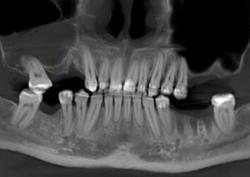

1. Предварительная диагностика — гарантия точного результата. Врач проводит осмотр, делает КТ. Это позволяет оценить объём костной ткани, расположение синусов и спланировать вмешательство так, чтобы оно прошло максимально безопасно и эффективно.

• Проводится рентген-диагностика и КТ, при необходимости — с использованием технологий искусственного интеллекта для детальной оценки объёма кости и расчёта оптимального подхода.

• Точная 3D-диагностика (КТ). Объёмная визуализация позволяет увидеть высоту кости, анатомию пазухи, что делает операцию максимально безопасной.

• Цифровое планирование операции. Хирург заранее моделирует объём костной ткани и этапы вмешательства, что снижает риски и сокращает длительность процедуры.